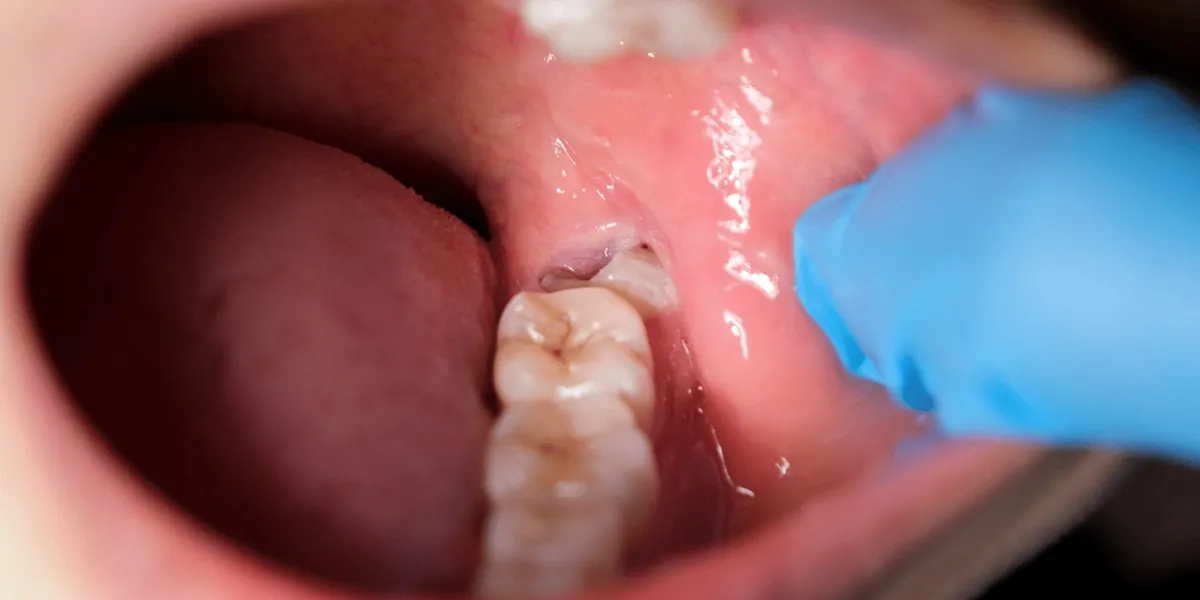

در اکثر موارد، دندان عقل بالا به دلیل دسترسی بهتر و فشار کمتر بر فک و بافتهای اطراف، گزینهای کمخطرتر برای بیماران قلبی به شمار میآید. دندان عقل پایین، به خصوص در موارد نهفته یا نیمه نهفته، میتواند باعث درد شدید، خونریزی بیشتر و طولانی شدن عمل شود که برای بیمار قلبی خطرناک است.

میزان نهفتگی دندان: دندان عقل پایین بیشتر دچار نهفتگی کامل یا جزئی است و این موضوع عمل را دشوارتر میکند.

قدرت دسترسی دندانپزشک: دندان عقل بالا معمولاً دسترسی آسانتری دارد و دید مستقیم دندانپزشک، کشیدن را سریعتر و کمدردتر میکند.

مطالعات بالینی نشان دادهاند که دندان عقل پایین، حتی در افراد سالم، نیازمند اعمال فشار بیشتر، برش گستردهتر لثه و گاهی تراشیدن استخوان است تا دندان از جای خود خارج شود. این مراحل پیچیده در بیماران قلبی میتواند باعث افزایش استرس، تحریک سیستم قلبی و فشار خون و حتی تشدید علائم قلبی شود، که نیازمند مراقبت ویژه و مدیریت دقیق است. از سوی دیگر، دندان عقل بالا، به دلیل ریشههای سادهتر، عدم پیچیدگی ساختار و دسترسی مستقیمتر برای دندانپزشک، کشیدن آسانتر و کمدردتری دارد، میزان استرس بیمار کاهش مییابد و طول مدت عمل کوتاهتر و ایمنتر میشود. این تفاوتها اهمیت مشاوره پیش از عمل و برنامهریزی دقیق دندانپزشکی را برجسته میکنند و تجربه بیمار را تا حد زیادی بهبود میبخشند.

وضعیت نهفتگی و پیچیدگی ریشهها نقش مهمی در راحتی و ایمنی کشیدن دندان عقل دارند. دندانهای عقل پایین معمولاً ساختار پیچیدهتر و ریشههای بلندتری دارند که فرایند کشیدن را دشوار و زمانبر میکند. این موضوع به ویژه برای بیماران قلبی اهمیت دارد، زیرا فشار و استرس اضافی میتواند عوارض قلبی ایجاد کند و نیازمند مدیریت دقیق است.

- دندان عقل پایین معمولاً ریشههای بلند و پیچیدهتری دارد که کشیدن آن را دشوار میکند.

- نزدیکی ریشههای پایین به عصبها ممکن است خطر آسیب عصبی بعد از عمل را افزایش دهد.

- دندانهای عقل بالا، به ویژه زمانی که نهفته نیستند، کمتر دچار پیچیدگی ریشه هستند و کشیدن آنها سریعتر، کمدردتر و ایمنتر است.